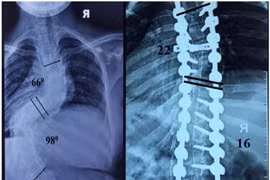

(khoahocdoisong.vn) - Biến dạng cột sống rất nặng và cứng nên bắt buộc phải phẫu thuật 2 đường. Phẫu thuật giúp chỉnh cong vẹo, trẻ cao thêm được 11-13cm. Hãy nhận biết các dấu hiệu trẻ bị biến dạng cột sống để cho trẻ đi khám sớm.